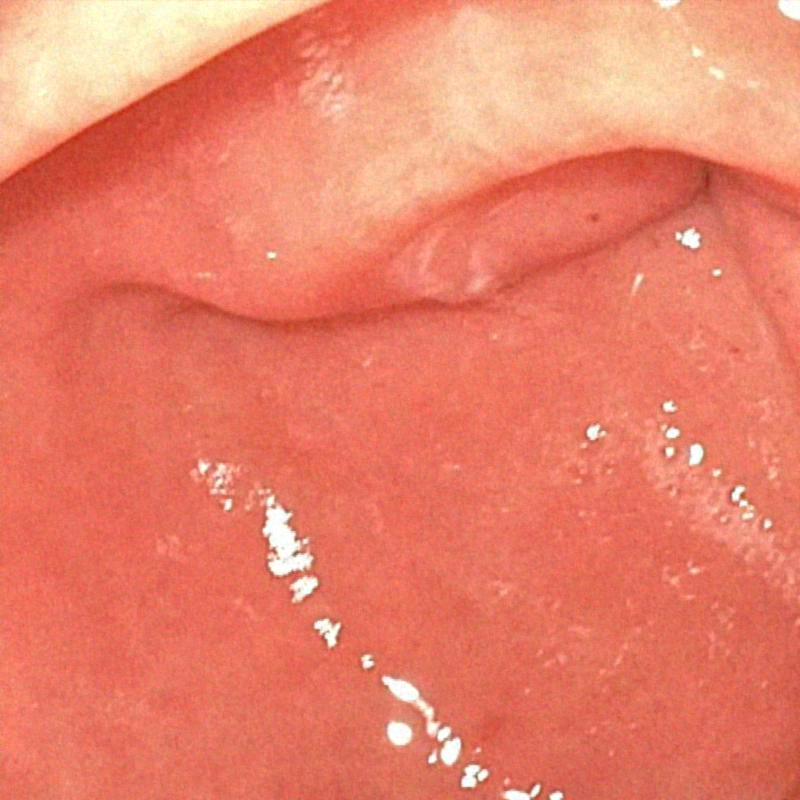

The proposed method was evaluated on a synthetic dataset. All deep learning-based methods were fine-tuned based on E-kvasri. Figure 2 presents sample results of the proposed method and comparative methods on four endoscopic images from the E-kvasri.

| (a) Input | (b) LIME | (c) HDRNet | (d) LECCM | (e) SwinIR | (f) NAFNet | (g) EndolMLE | (h) Ours | (i) GT |